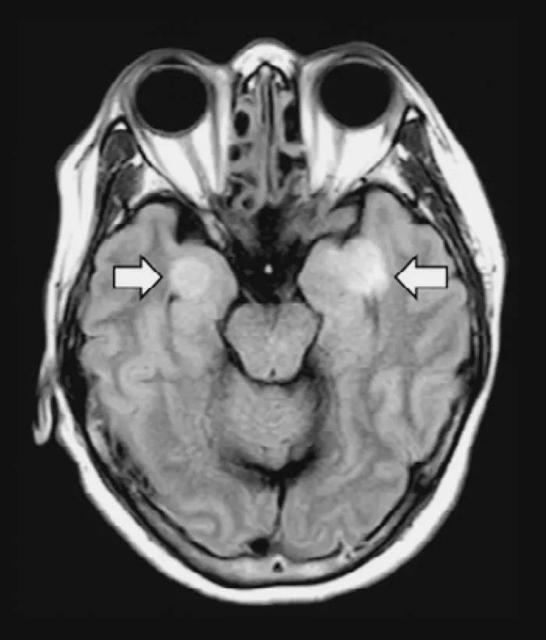

治疗96小时后(起病第14天),患者出现颌面及口角频繁抽搐,伴持续呃逆,医生查体发现颈抵抗阳性,双侧瞳孔等大等圆,对光反射迟钝,四肢肌张力升高,双侧膝反射亢进,双侧巴氏征及踝阵挛阳性,头颅CT颅内未见异常,测脑嵴液压力大于330mmH2O,脑嵴液外观无色清亮,生化检测无异常。北京地坛医院重症医学科、检验科及中国疾控中心传染病所联合工作组对采集的脑嵴液标本进行宏基因组二代测序、鉴定可能的感染病原体过程中,排除了其他病原体,获得了SARS-CoV-2病毒基因组序列。通过基因测序证实脑嵴液中存在SARS-CoV-2,临床诊断病毒性脑炎。